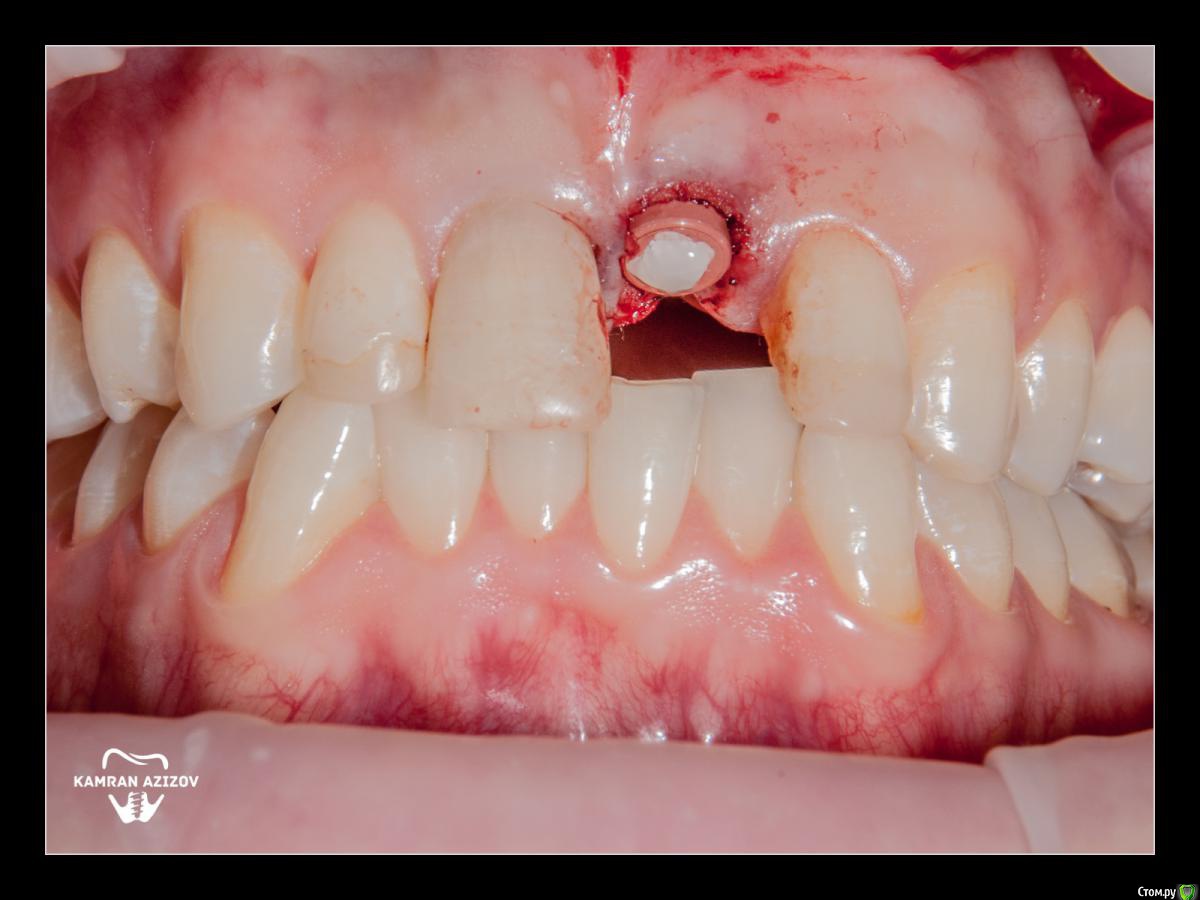

Dman Опубликовано 11 октября, 2019 Поделиться Опубликовано 11 октября, 2019 На 9 фото не понятно что, другой формирователь и корректировал десну? Ссылка на комментарий

kamranchick Опубликовано 11 октября, 2019 Автор Поделиться Опубликовано 11 октября, 2019 На 9 фото не понятно что, другой формирователь и корректировал десну?да. это такой формирователь на штраумане который винтом прикручивается, денег не было на времянку, пришлось поставить такой формик Ссылка на комментарий

Dman Опубликовано 11 октября, 2019 Поделиться Опубликовано 11 октября, 2019 да. это такой формирователь на штраумане который винтом прикручивается, денег не было на времянку, пришлось поставить такой формикс десной то что делали - выглядит как корректированная бором или лазером Ссылка на комментарий

kamranchick Опубликовано 12 октября, 2019 Автор Поделиться Опубликовано 12 октября, 2019 Не. Ничего особо не делал.Формик зарос. Немного освободил от мягких тканей. Чуть чуть скальпелечком прошёл и вкрутил Новый Ссылка на комментарий